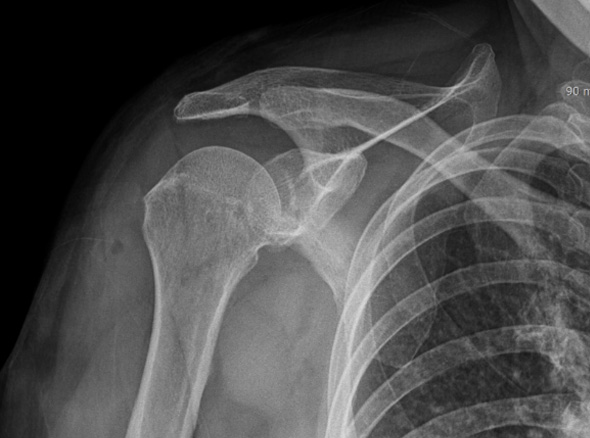

관절 내시경을 통한

견봉 성형술

관절 내시경을 통하여

힘줄 손상을 유발하는 견봉하 골극을 제거합니다.